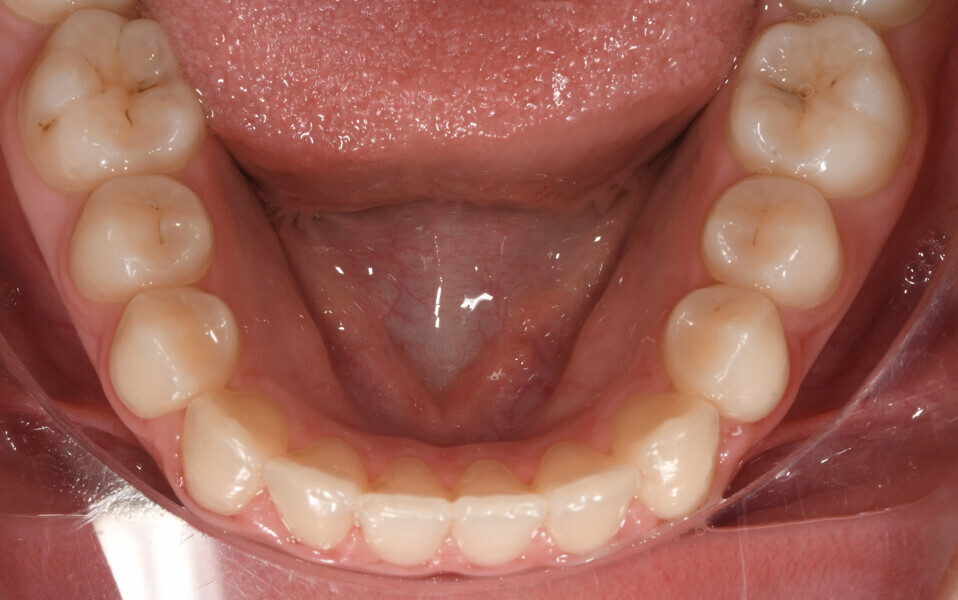

Fig. 2: Facial and intra-oral photographs after treatment with fixed orthodontic appliances.

Fig. 3: Facial and intra-oral photographs after treatment with fixed orthodontic appliances.

Fig. 4: Facial and intra-oral photographs after treatment with fixed orthodontic appliances.

Fig. 5: Facial and intra-oral photographs after treatment with fixed orthodontic appliances.

Fig. 6: Facial and intra-oral photographs after treatment with fixed orthodontic appliances.

Fig. 7: Facial and intra-oral photographs after treatment with fixed orthodontic appliances.

Fig. 8: Facial and intra-oral photographs after treatment with fixed orthodontic appliances.

Fig. 9: Facial and intra-oral photographs after treatment with fixed orthodontic appliances.

Fig. 10: Facial and intra-oral photographs after treatment with fixed orthodontic appliances.